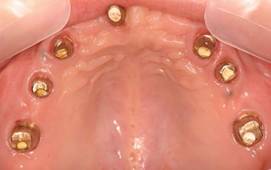

白金加金のアバットメント(土台)

上顎

術後。上部構造はハイブリッドレジンです。しっかり嚙めるようになり喜んでいただきました。